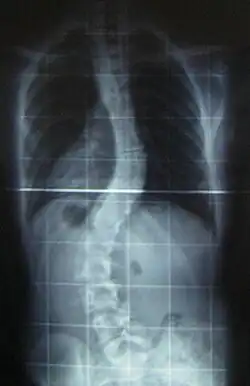

- Contractures Characteristically, bilateral contractures of the proximal joints of the upper extremities (shoulder and elbows) and proximal joints of the lower extremities (hips and knees). Spine contractures in the form of progressive scoliosis occurs and occasionally contracture of neck musculature also known as torticollis.[10]

Scoliosis, which is a sideways curve of the persons vertebrate, is determined by a variety of factors, including the degree (mild or severe), in which case if possible a brace might be used by the individual.[15]